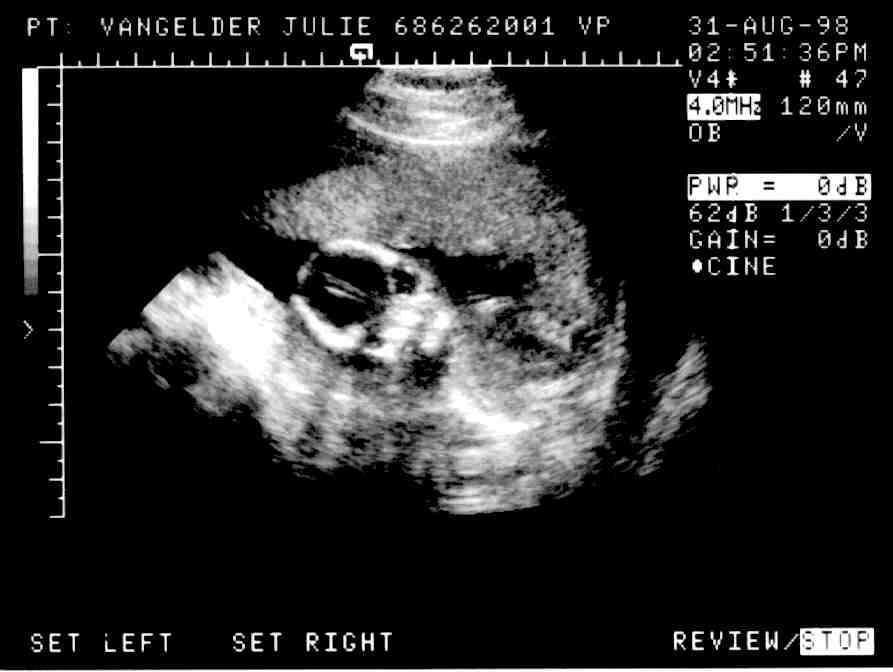

Junior at 16 weeks

Here's Junior looking at you! Junior's heartbeat is a steady 140/minute. Junior's favorite pastime is kicking Mom in the stomach.

Sonogram